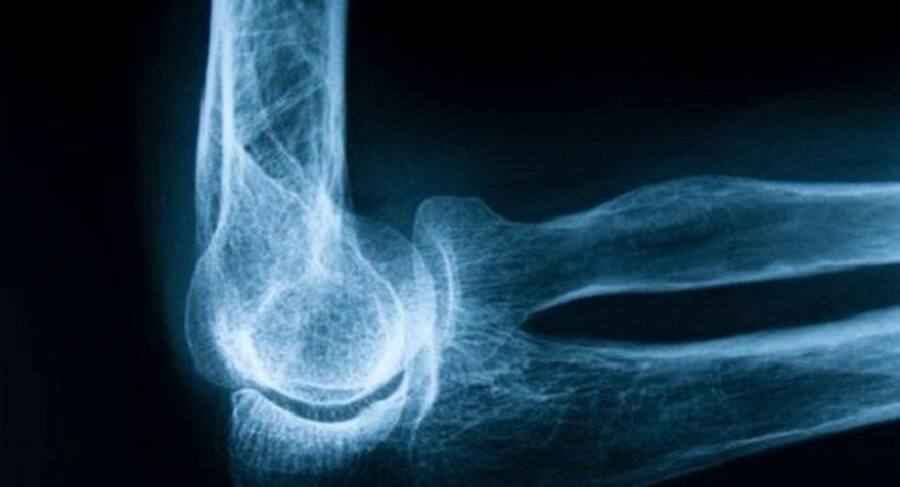

While its prescription is increasing rapidly worldwide, the safety profile of tramadol, such as risk of fracture, remains unclear. © Shutterstock

Several professional organizations have recommended tramadol as one of the first line or second line therapies for patients with chronic noncancer pain. While its prescription is increasing rapidly worldwide, the safety profile of tramadol, such as risk of fracture, remains unclear, the researchers noted.